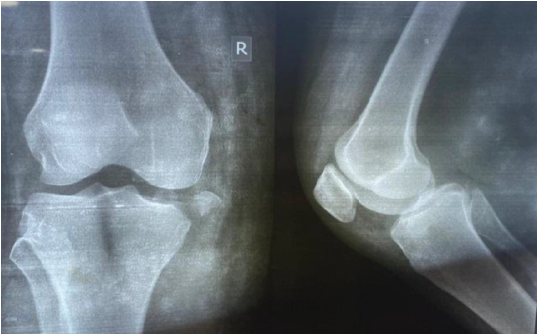

The optimal timing for surgery remains a subject of ongoing debate. Our findings are consistent with those of Harner et al. [6] and Mook et al. [19], as well as the recent meta-analysis by Vaishya et al. [24,32], support early reconstruction – ideally within 3 weeks – to facilitate graft placement and reduce arthrofibrosis risk. However, in cases with severe soft tissue compromise or delayed presentation, often seen in rural LMIC contexts, delayed surgery may be unavoidable. Yoon et al. [8] highlights that while delayed intervention can still yield acceptable results, early timing is associated with faster neuromuscular recovery. In our cohort, single-stage reconstruction yielded excellent functional outcomes without increasing complication rates, aligning with the findings of Ishibashi et al. [5] and Joutoku et al. [4]. Recent systematic reviews [26,29] indicate that single-stage procedures reduce hospital stay, rehabilitation time, and costs – critical advantages in LMIC settings. Staged approaches remain indicated for cases with severe swelling, vascular repair, or open injuries [14,16], but their higher rehabilitation demands and resource implications make them less feasible in many environments. Graft selection remains a critical factor in MLKI reconstruction. The STG autografts were our primary choice; PL autografts were used when the quality of the hamstring was found to be suboptimal, a finding also supported by Goyal et al. [10]. Moreover, a recent systematic review [31] demonstrates comparable biomechanical strength and functional outcomes. Our findings of no significant difference in outcomes between fixation methods are consistent with those of Crum et al. [11] and recent biomechanical analyses [25]. Graft choice should remain individualized, taking into account the patient’s anatomy, prior surgeries, and the availability of suitable grafts. We followed a medial or posterolateral repair-first strategy, followed by reconstruction of the PCL and ACL. Excellent clinical outcomes were seen with this approach (Fig. 2, 3, 4, 5). This sequence, supported by Kim et al. [9] and LaPrade et al. [18], restores coronal stability before addressing sagittal stability, minimizing graft tension imbalances. Literature suggests that sequencing errors can compromise biomechanical restoration [27], emphasizing the need for standardized, biomechanically informed protocols.

Figure 2: Anteroposterior and lateral view of radiograph of the knee showing medial condyle fracture with medial collateral ligament avulsion.